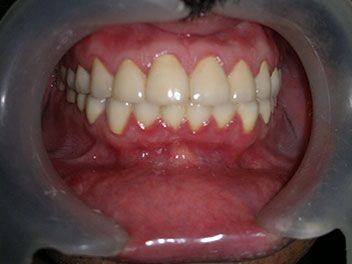

Orthodontic Alignment with Ceramic Brackets